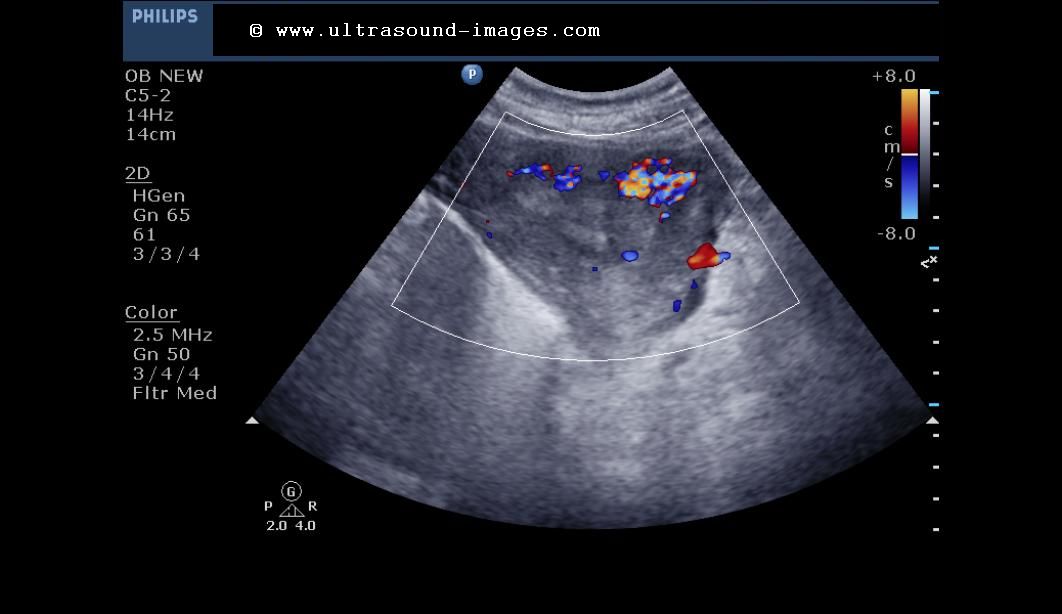

Sonography retained products of conception

Best predictors of grayscale ultrasound combined with color Doppler in Retained Products Of Conception Radiology Assistant retained products of conception (rpoc) generally result after first half of pregnancy termination and also may occur after. retained products of conception (rpocs) are among the most common causes of secondary postpartum, postmiscarriage, and. retained products of conception (pocs) can occur after spontaneous or induced abortion and after. retained products of conception (rpoc) are a common. Retained Products Of Conception Radiology Assistant.